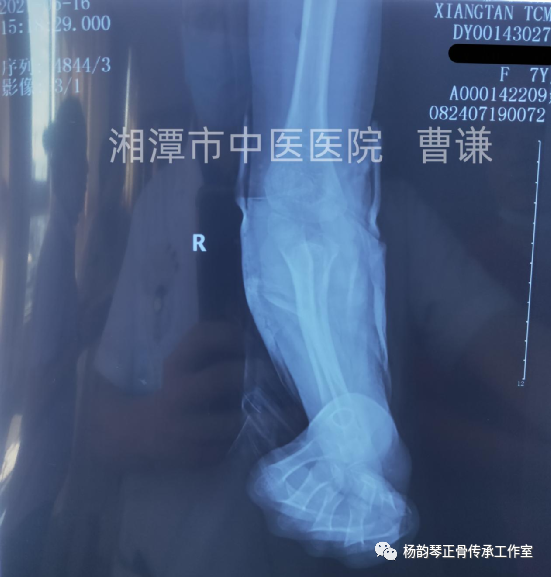

伤后半月余复查骨折对位对线良好,肱桡关节匹配良好,改直角托板固定,每次换药进行被动肘关节屈伸锻炼,这样有利于促进关节功能早期恢复。

伤后近一月拍片复查骨折愈合良好,肱桡关节匹配正常。